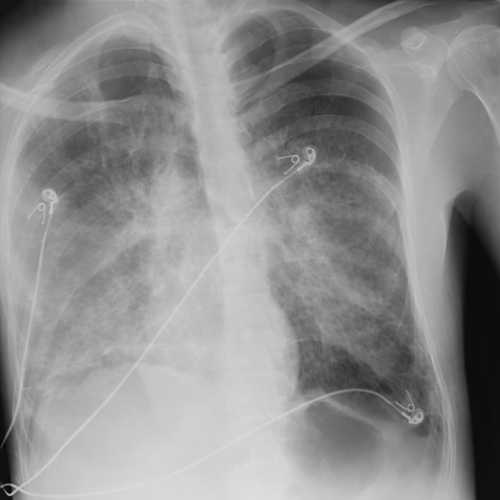

Posteriormente, el paciente presenta deterioro súbito con incremento de presiones ventilatorias y desaturación, realizándose radiografía de tórax donde se identifica neumotórax izquierdo, compatible con barotrauma secundario a ventilación mecánica.

Este evento condiciona un punto crítico en la evolución, incrementando significativamente el riesgo de mortalidad.

El desarrollo de SDRA refleja daño alveolar difuso, mientras que la formación de neumatoceles condiciona fragilidad estructural pulmonar. La ventilación mecánica, aunque necesaria, incrementa el riesgo de ruptura alveolar, desencadenando barotrauma.

La aparición de neumotórax representa un punto de inflexión crítico, ya que complica el manejo ventilatorio y se asocia a alta mortalidad.

El desarrollo de neumotórax en este contexto representa una complicación grave que impacta directamente en el pronóstico, subrayando la necesidad de estrategias ventilatorias protectoras y manejo multidisciplinario.